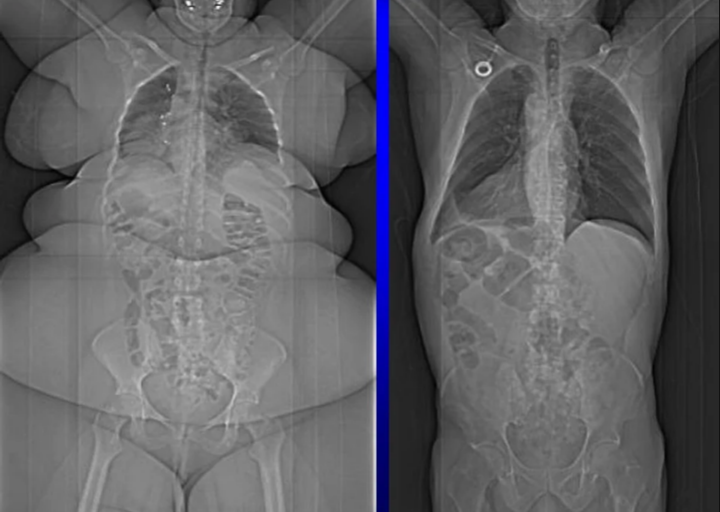

7. Порівняння рентгенівських знімків повної людини та поганого